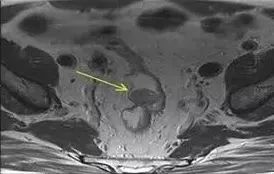

直肠神经内分泌瘤需要做CT/MRI么?

答:由于直肠神经内分瘤仍是低度恶性的肿瘤,即使不足1 cm的肿瘤,也有2%~3%的可能性发生转移,主要是肠周、盆腔淋巴结和肝脏,因此原则上建议做腹部CT和盆腔MRI或CT,排除转移。

图片